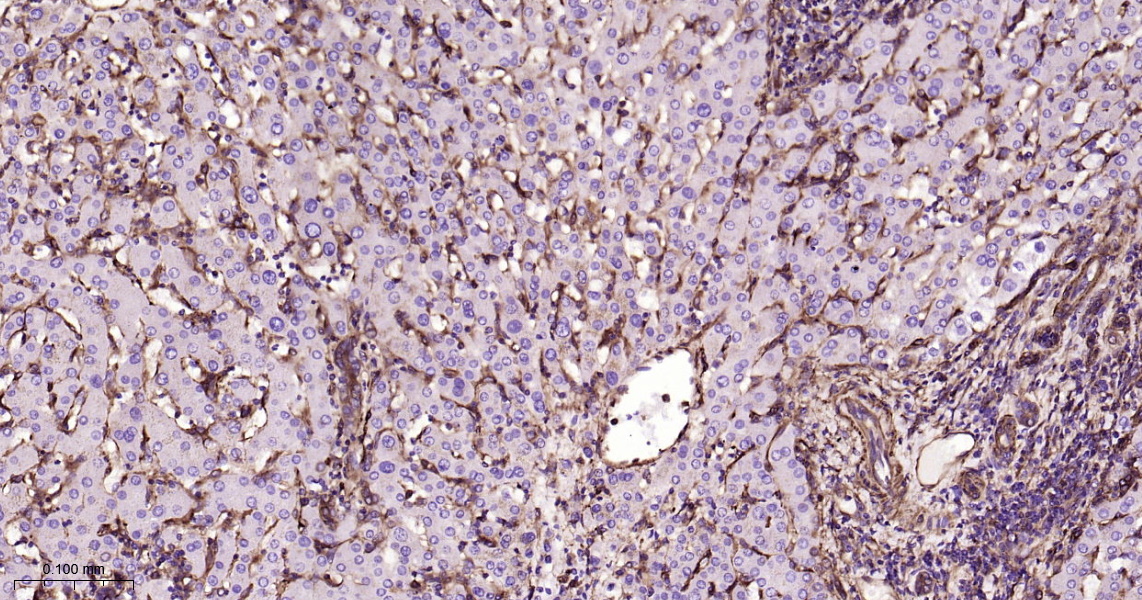

• IHC-P

IHC-P IHC-P1:100-500